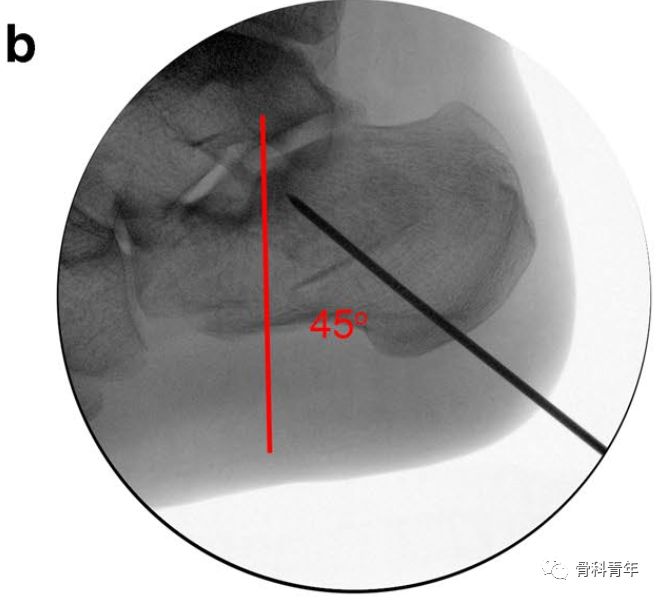

采用血管钳及克氏针撬拨,后关节面恢复有限,后关节面仍存在台阶(图中绿线所示)。

采用撑开器可实现后关节面的复位。